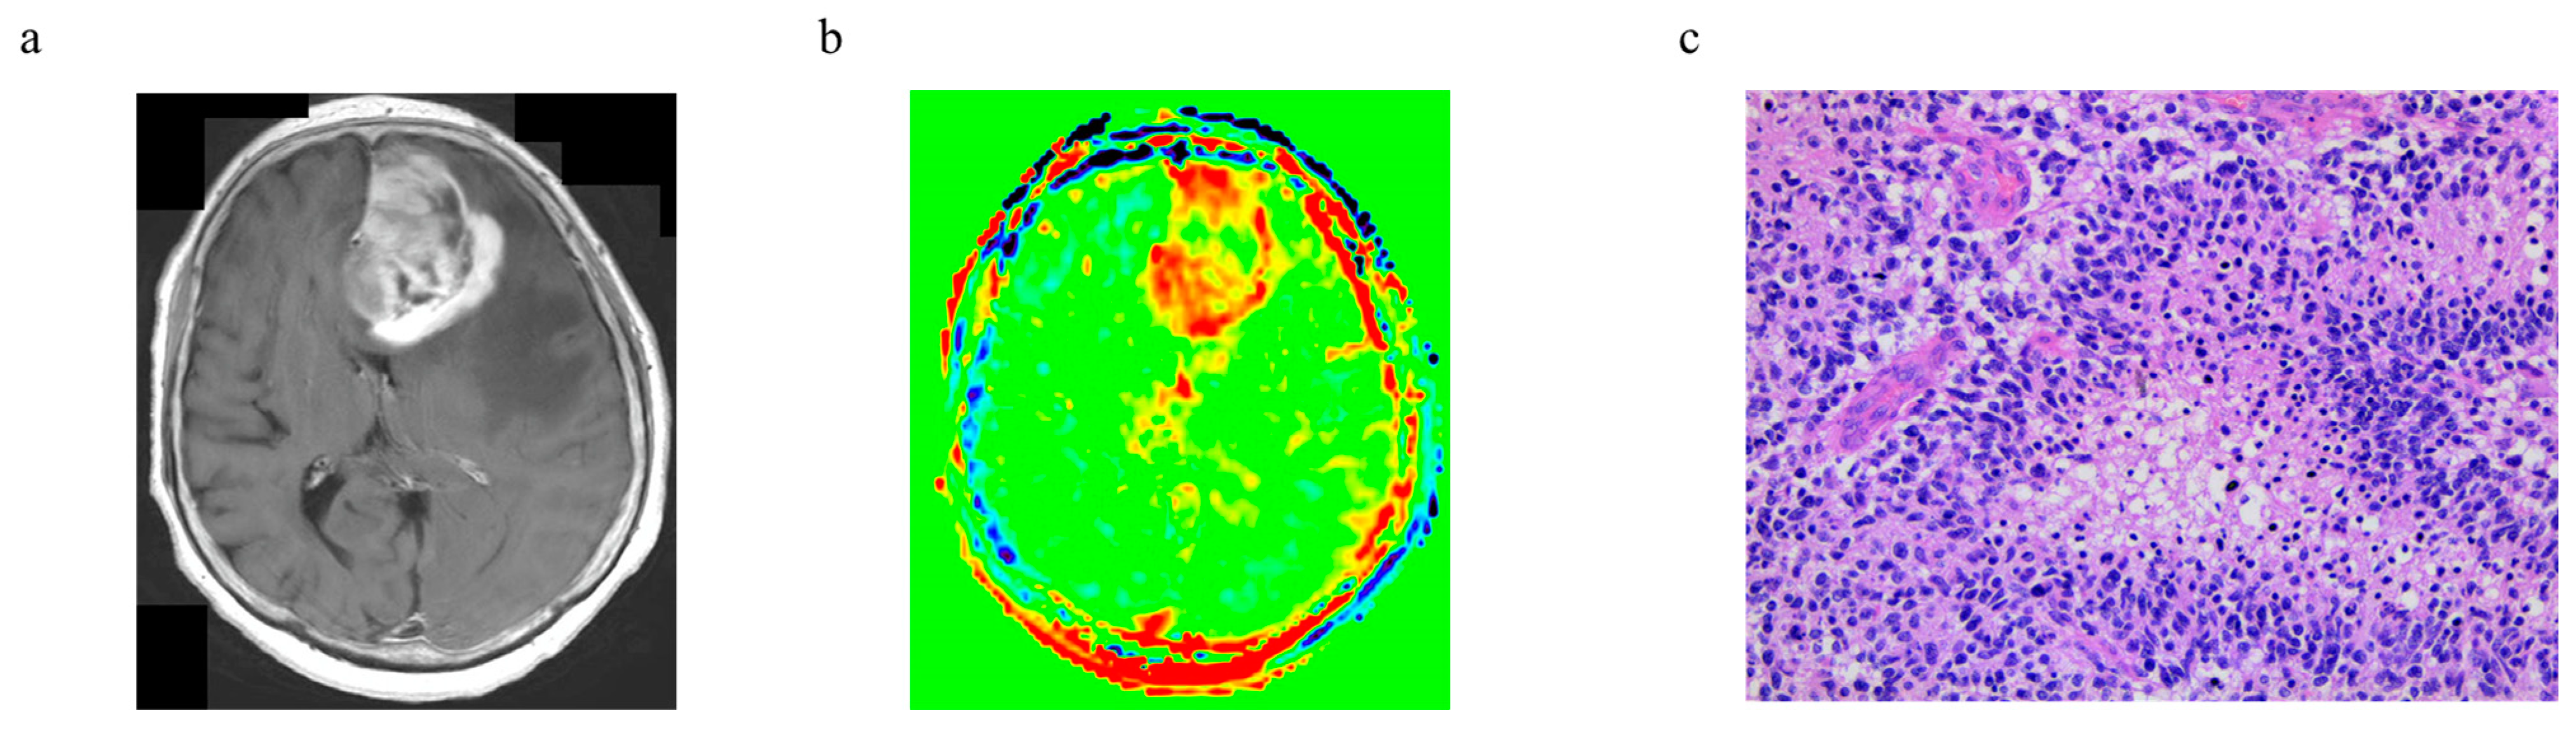

3.6. Representative Cases